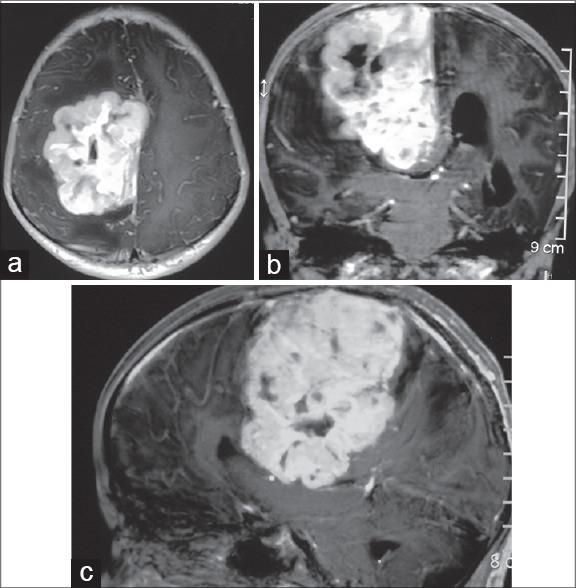

Ependymoma tends to occur commonly along either on ventricular surfaces of the brain or central canal of the spinal cord. Rarely, ependymoma can develop in the cerebral cortex without attachment to the ventricular structures. However, such occurrence in the purely extra-axial compartment in the falcine region mimicking falcine meningioma is exceedingly rare. The detailed search of primary falcine ependymoma (PEFE) in Medline and PubMed yielded only five isolated case reports. All cases occurred in patient older than 17 years of age; however, our case was a 9-year-old girl. PEFE tends to occur more commonly in male with a male to female ratio of 3:2, with the mean age of 28.8 years (range 17-43 years), lesion had intra-operatively had solid consistency in all cases. All cases were subjected to surgical resection followed by adjuvant radiotherapy; however, in addition, one case also received chemotherapy, with an average follow-up period of 9 months, however, missing in one case. The mean size of the tumor was 5.25 cm (range 1.8-7.2 cm). The authors present a unique case of PEFE in a 9-year-old girl with 8.6 cm ×6 cm ×5.4 cm-sized giant primary falcine ependymoma, managed surgically successfully. To the best of the authors' knowledge, the current case is the first case of pediatric extra-axial falcine ependymoma occurring within the first decade of life in the western literature, showing rapid evolution over 1½ month's period into a giant size. Brief pathogenesis, clinical feature, and management along with the pertinent literature are reviewed briefly.

摘要

室管膜瘤通常易于发生在脑室内表面或脊髓中央管。罕见的是,室管膜瘤可在大脑皮质中发生而不附着于脑室结构。然而,在镰状区域的纯轴外间隙中发生这种类似镰状脑膜瘤的情况极为罕见。在医学文献数据库(Medline)和医学期刊数据库(PubMed)中详细检索原发性镰状室管膜瘤(PEFE)仅得到5例孤立的病例报告。所有病例均发生在17岁以上的患者中;然而,我们的病例是一名9岁女孩。PEFE在男性中更常见,男女比例为3:2,平均年龄为28.8岁(范围17 - 43岁),所有病例术中病变质地均为实性。所有病例均接受了手术切除,随后进行辅助放疗;然而,此外,1例还接受了化疗,平均随访期为9个月,但有1例失访。肿瘤的平均大小为5.25厘米(范围1.8 - 7.2厘米)。作者报告了一例独特的PEFE病例,患者为一名9岁女孩,患有大小为8.6厘米×6厘米×5.4厘米的巨大原发性镰状室管膜瘤,手术治疗成功。据作者所知,目前该病例是西方文献中首例发生在生命第一个十年内的小儿轴外镰状室管膜瘤,在1个半月的时间内迅速发展为巨大肿瘤。本文简要回顾了其简要发病机制、临床特征、治疗方法以及相关文献。